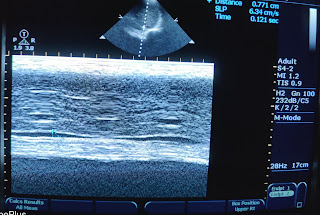

USG abdomen -